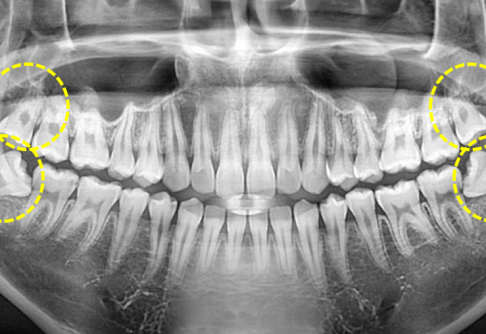

Before

After

위 치료 사례는 굿프렌즈치과에서 직접 치료를 받은 환자 분의 사례로 직접 동의를 얻어 게재되었습니다.

치료사례 더보기 +